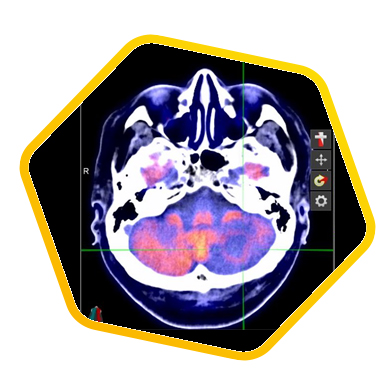

双示踪剂PET/CT (F-18 FDG及Ga-68 DOTATATE) 用於评估脑神经内分泌肿瘤体内的扩散情况

![]() [F-18] FDG |

![]() [Ga-68] DOTATATE |